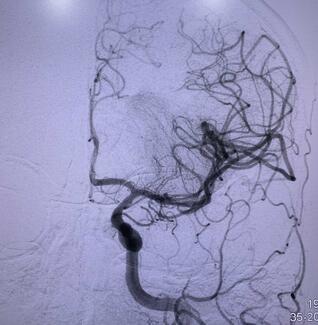

This case report highlights the clinical trajectory of a previously healthy young man who presented with acute right hemiplegia due to left middle cerebral artery occlusion. The patient underwent successful mechanical thrombectomy.